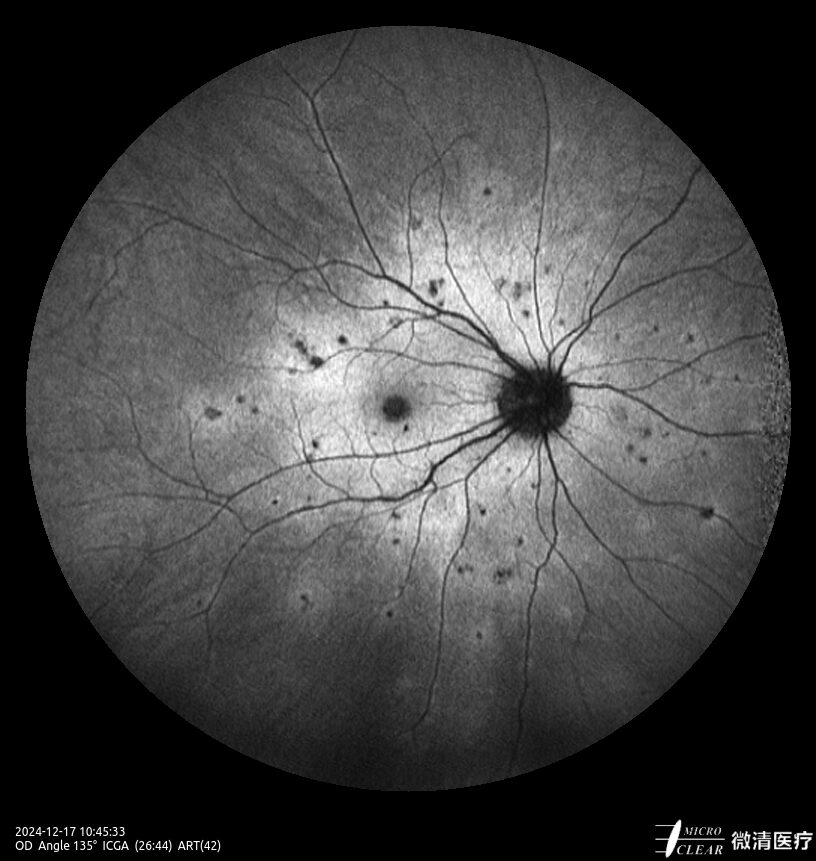

- 135° WA (Groothoekangiografie) – in één opname

Confocale Scanning Laser Oftalmoscoop (CSLO)

- Combinatie van drie confocale laserbronnen voor maximaal contrast en getrouwheid.

- Verbeterd confocaal ontwerp zorgt voor een betere scheiding van de netvlieslagen en verbeterde penetratie door cataract en oculaire troebelingen.